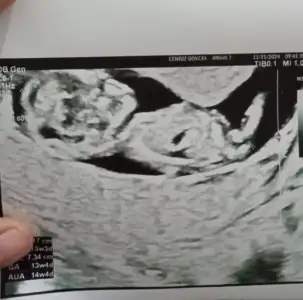

Nub teorisine göre bebeğimin cinsiyeti?

Benim minnoşuma da bakar mısınız 13 haftalık❤️